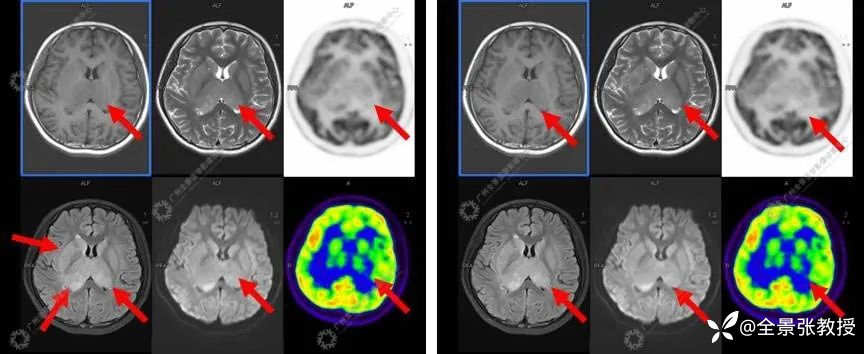

显示:双侧尾状核头-体部、双侧豆状核、双侧丘脑-漏斗-垂体柄、双侧颞叶海马-海马旁回可见对称性异常信号,T1WI呈稍低信号,T2WI及T2W-FLAIR呈稍高信号,DWI大部分呈等信号,右侧丘脑见小片状弥散轻度受限区,SWI未见出血信号;双侧丘脑肿胀,体积增大;MR波谱成像示双侧背侧丘脑NAA峰明显减低,Cho峰升高;双侧尾状核、豆状核各峰尚可,上述部位MR灌注减低,相应脑区FDG摄取对称性弥漫性减低,SUVave为2.92,其中右侧丘脑后缘见小条片状FDG摄取稍高,SUVmax为6.23。

诊断结果为:双侧尾状核头-体部、双侧豆状核、双侧丘脑-漏斗-垂体柄、双侧颞叶海马-海马旁回对称性异常信号,且MRI灌注及糖代谢弥漫性明显减低,提示局部脑功能受损明显;双侧丘脑肿胀;颅脑MRI波谱示病变区NAA峰明显减低,Cho峰升高,提示相应部位神经元受损;考虑中枢系统恶性肿瘤,弥漫性中线胶质瘤可能。后病理证实为H3K27M突变型弥漫性中线胶质瘤。